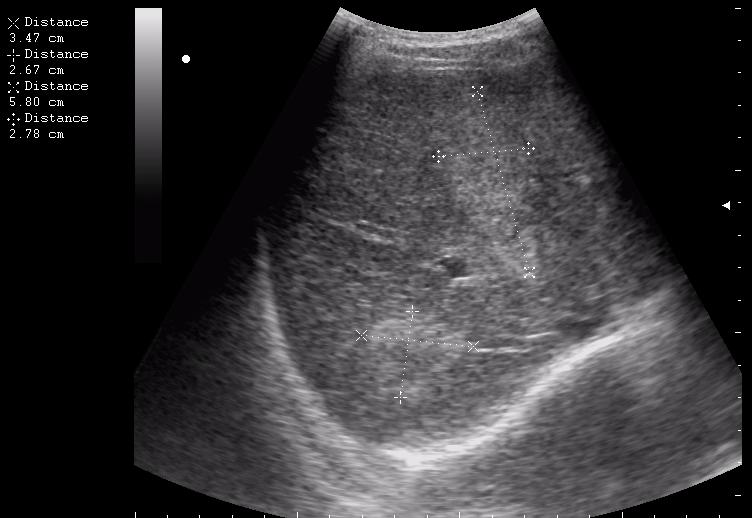

наезд большой черной Прады на маленькую (13кг) 5-летнюю девочку.

получает Медаксон, рабочая версия - изменение желчного пузыря вследствии травмы (шепотом - рекомендация хирургу сменить антибиотик)